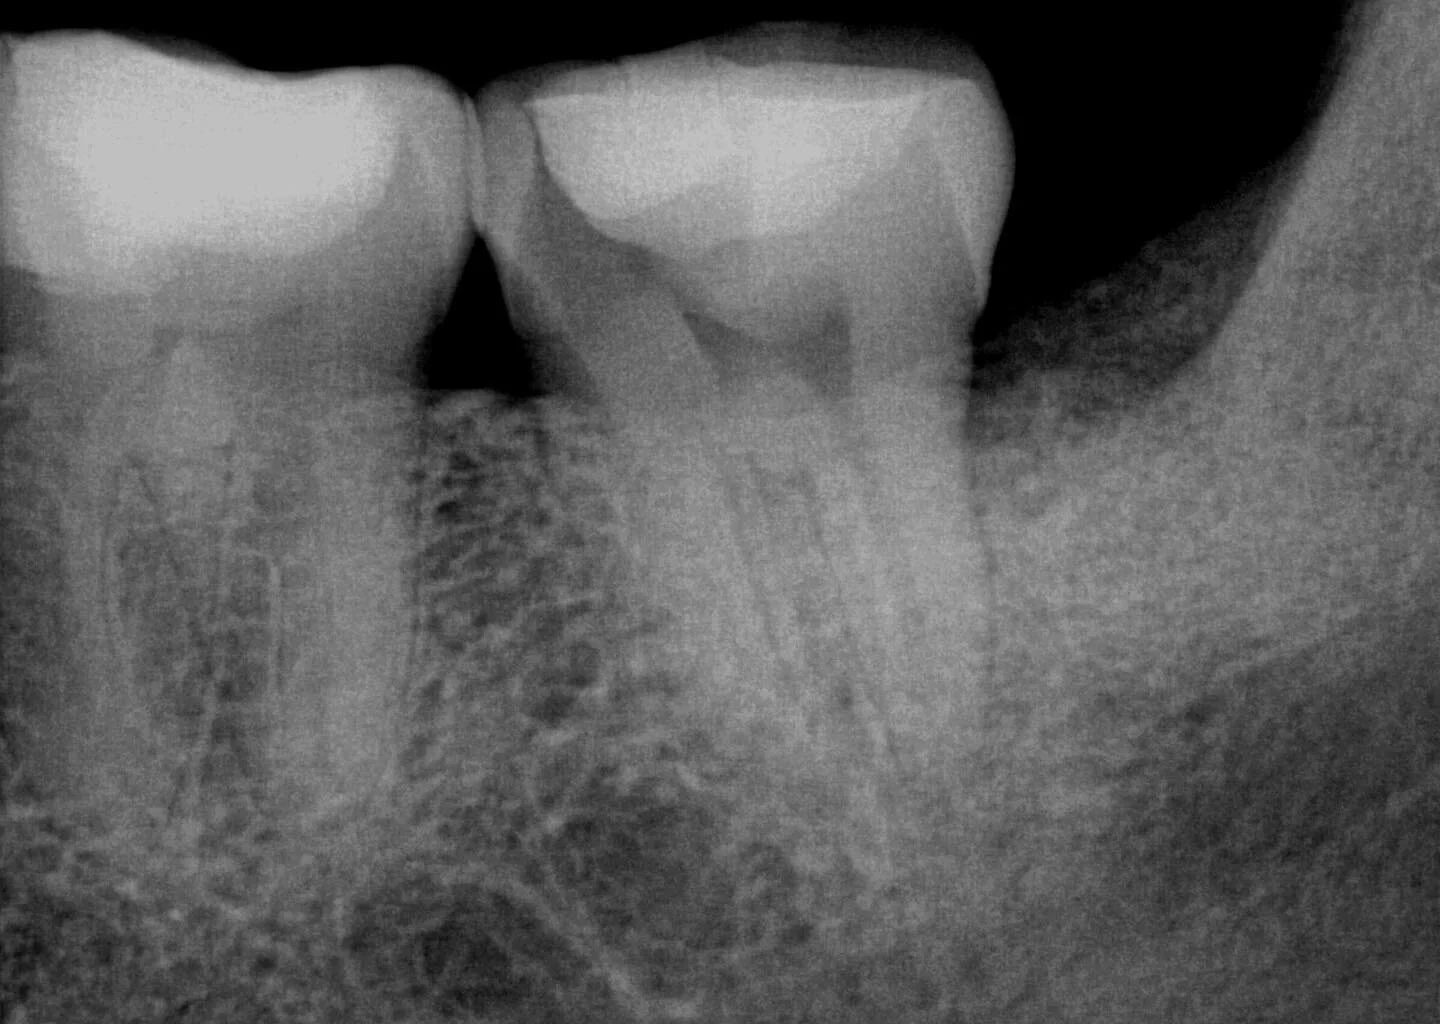

Dr. Zegar’s endodontic cases portfolio :